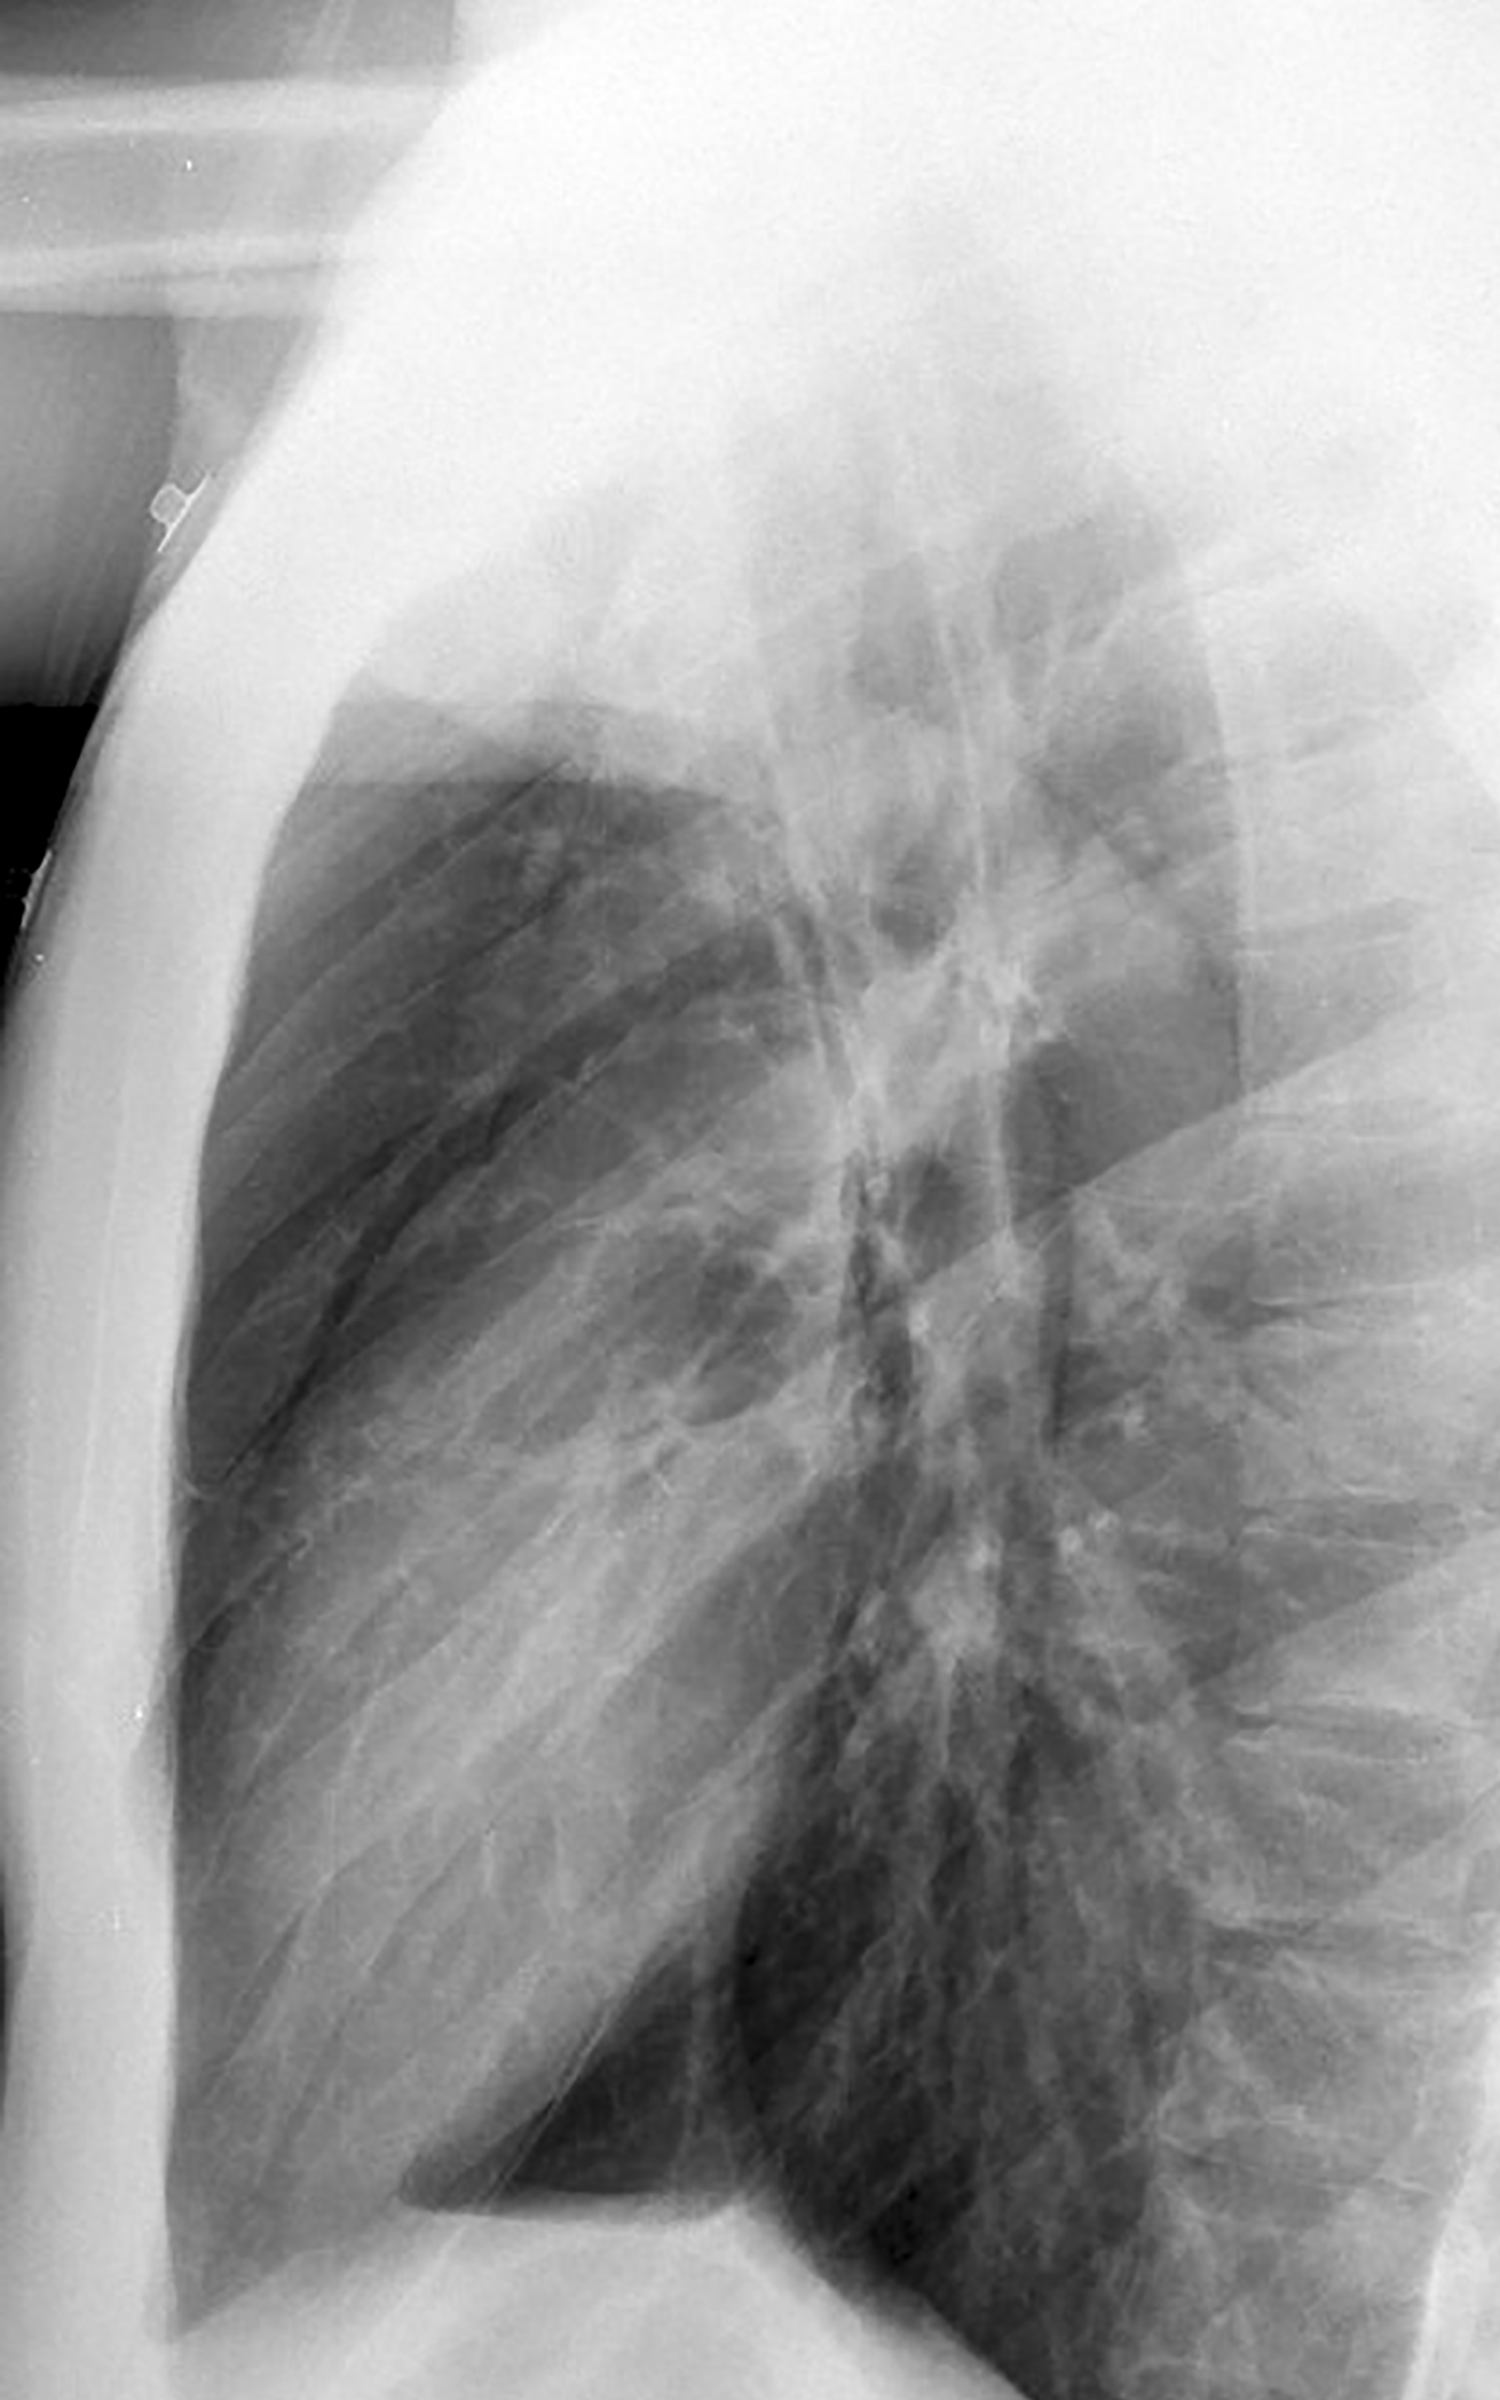

Asthma PnMed lat

Asthmatic pneumomediastinum lat